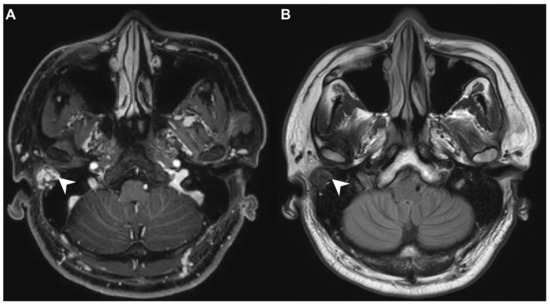

A 40-year-old male with hypertension was taking appropriate medication. He had suffered from right hearing impairment and aural fullness for two months. Examination with an otoscope revealed a smooth bulging mass with a non-epithelial defect on the right side that totally occluded the EAC (Figure 1). No otalgia, otorrhea, vertigo, or facial palsy was noted. There were no other lesions in the head-and-neck region. Audiological assessment revealed conductive hearing loss (pure-tone average) of 30 dB and an air-bone conduction gap of 20 dB on the right side, with preservation of bone conduction hearing. The laboratory data revealed a mildly elevated C-reactive protein level (7.44 mg/L; normal <5 mg/L) without leukocytosis (5400/µL; normal 3900–10,600/µL). As the EAC was occluded, high-resolution computed tomography (HRCT) was scheduled and revealed a submucosal soft tissue mass accompanied by partial mastoid bony destruction (Figure 2A,B). Magnetic resonance imaging (MRI) revealed a well-circumscribed mass in heterogeneous T1-weighted hyperintense (Figure 3A) and T2-weighted isointense (Figure 3B) images.

In our patient, HRCT of the temporal bone revealed a well-demarcated, submucosal nodular lesion in the right EAC with tiny bony internal fragments (Figure 2A,B). MRI is indicated when HRCT shows a tumor involved with adjacent EAC soft tissues. In our patient, MRI revealed a well-circumscribed mass in the EAC that was hyperintense in the T1 (with contrast) sequence but T2-isointense (Figure 3A,B). Noda et al., and Pons et al., reported similar findings; T1-weighted contrast-enhanced MRI enabled strong tumor enhancement [10,11].

Figure 3. (A) On magnetic resonance imaging (MRI), the T1-contrast sequence revealed a heterogeneous hyperintense mass in the right EAC (arrow). (B) On MRI, the T2-sequence yielded a well-circumscribed isointense signal from the mass (arrow).